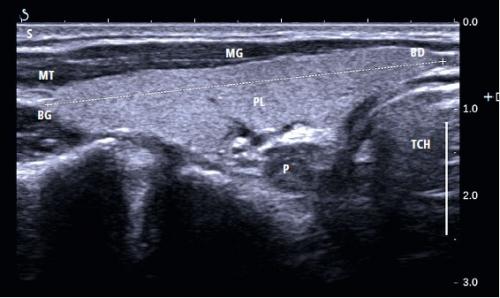

- Длина доли щитовидной железы – самое большое расстояние между ее верхним полюсом и нижним полюсом (рис. 5) . Она измеряется в продольном разрезе. Это наибольшее измерение, измеренное параллельно грудино-ключично-молочной мышце.

Левая доля щитовидной железы в продольном разрезе

Рис. 5. Левая доля щитовидной железы в продольном разрезе. Измеряется длина доли щитовидной железы (+). Анатомические структуры были отмечены: BG – верхний полюс щитовидной железы; БД – нижний полюс щитовидной железы (в трахее); MG – грудино-мышечная мышца; MT – грудно-щитовидная мышца; П – пищевод; PL – левая доля щитовидной железы; TCH – трахея.